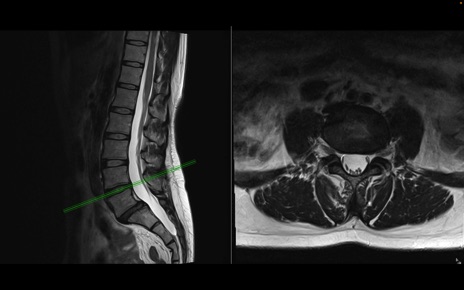

腰椎MRI

T2WI(横断像)

T2WI(矢状断像)